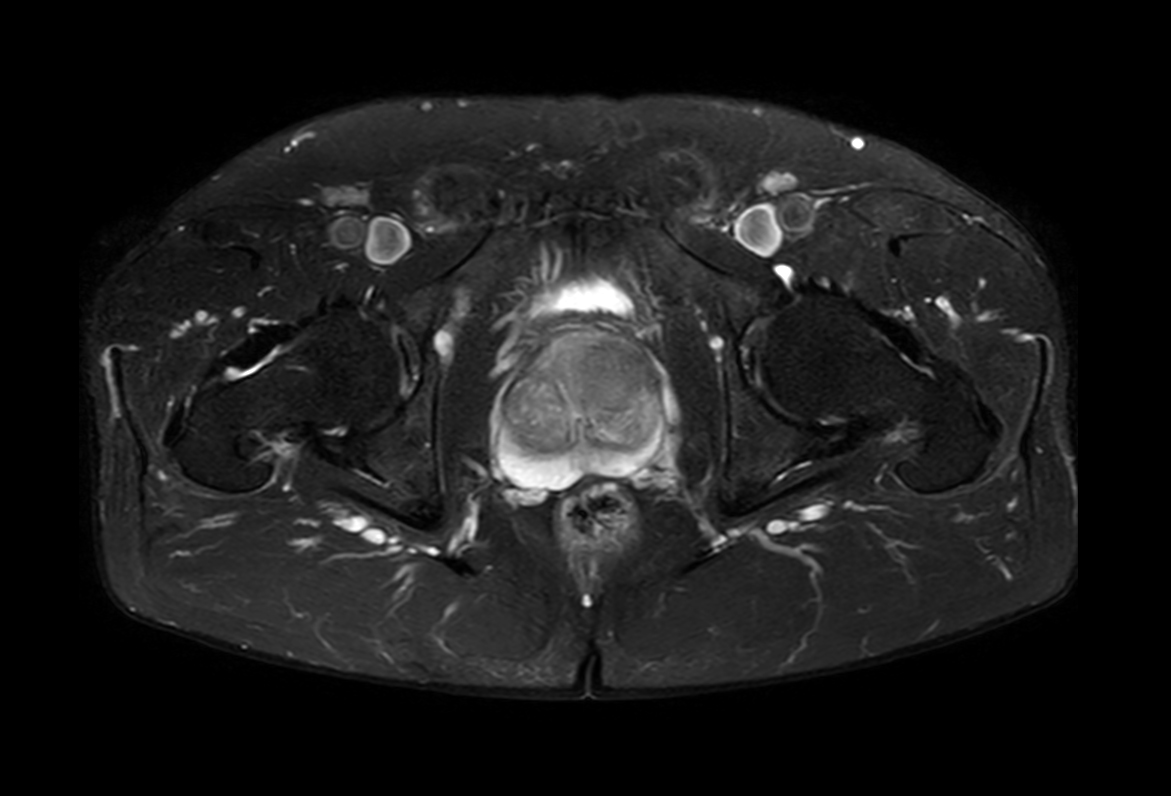

Axial T1w TSE